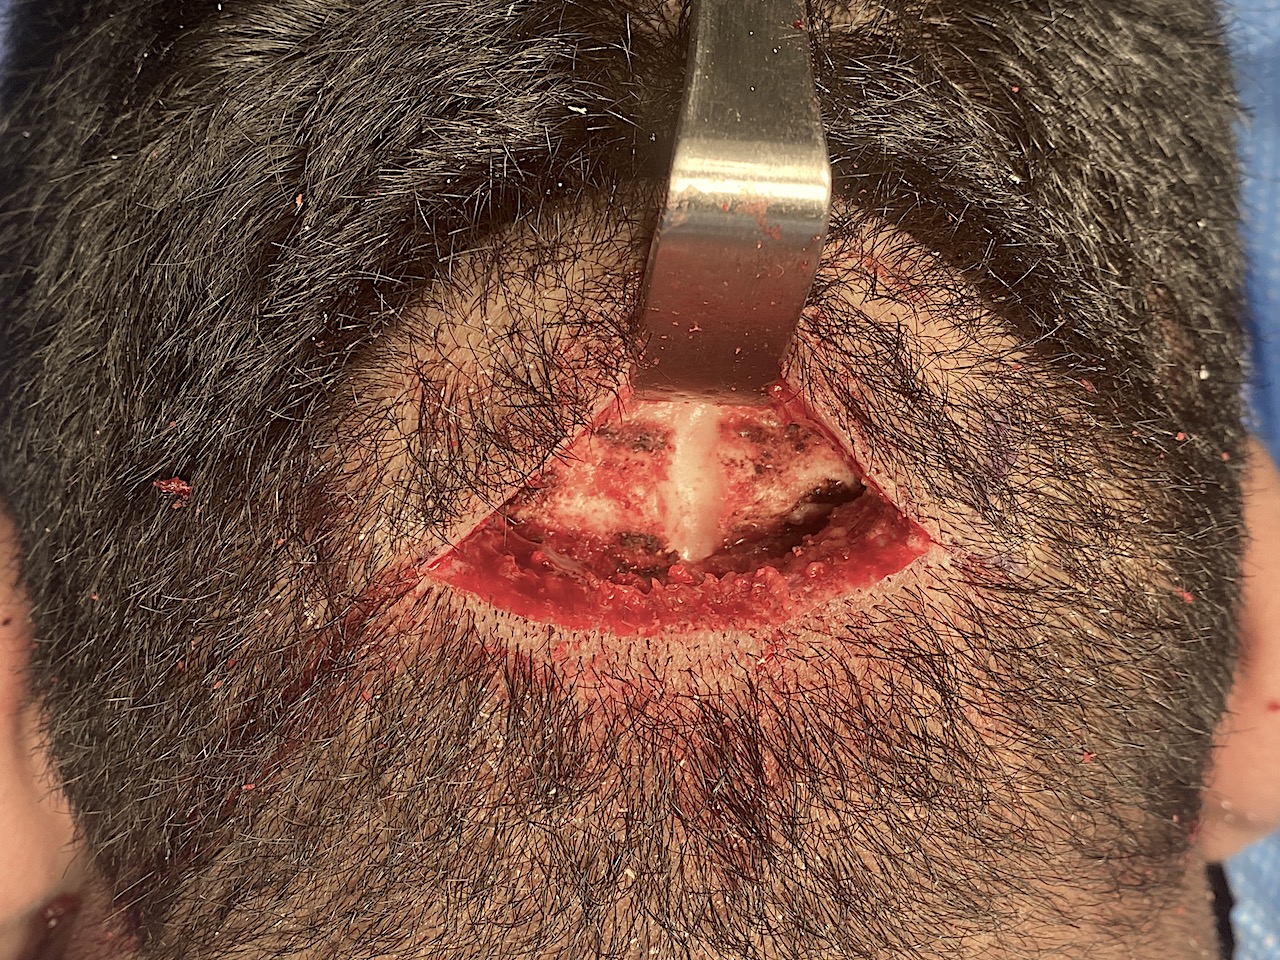

Desire for reduction of prominent occipital knob deformity.

Intraoperative result from occipital knob skull reduction through a direct small scalp incision.

Desire for reduction of prominent occipital knob deformity.

Intraoperative result from occipital knob skull reduction through a direct small scalp incision.